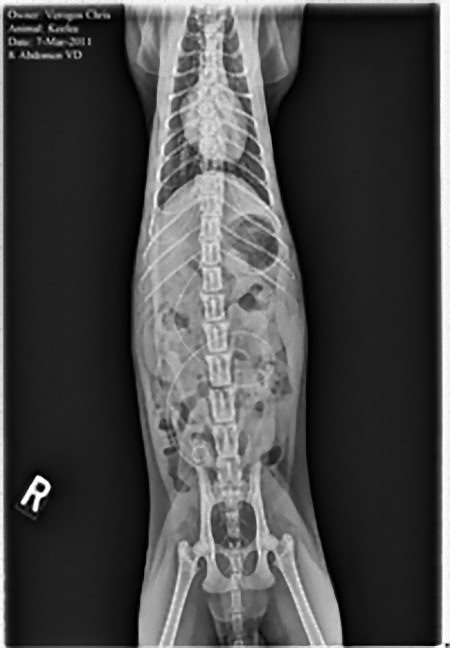

この画像を大きなサイズで見る準優勝写真:

12歳のビークル犬の体内に宿る、靴ひも、腐葉土、ストッキング、プラスチック、ネクタイと車用ブラシなど。